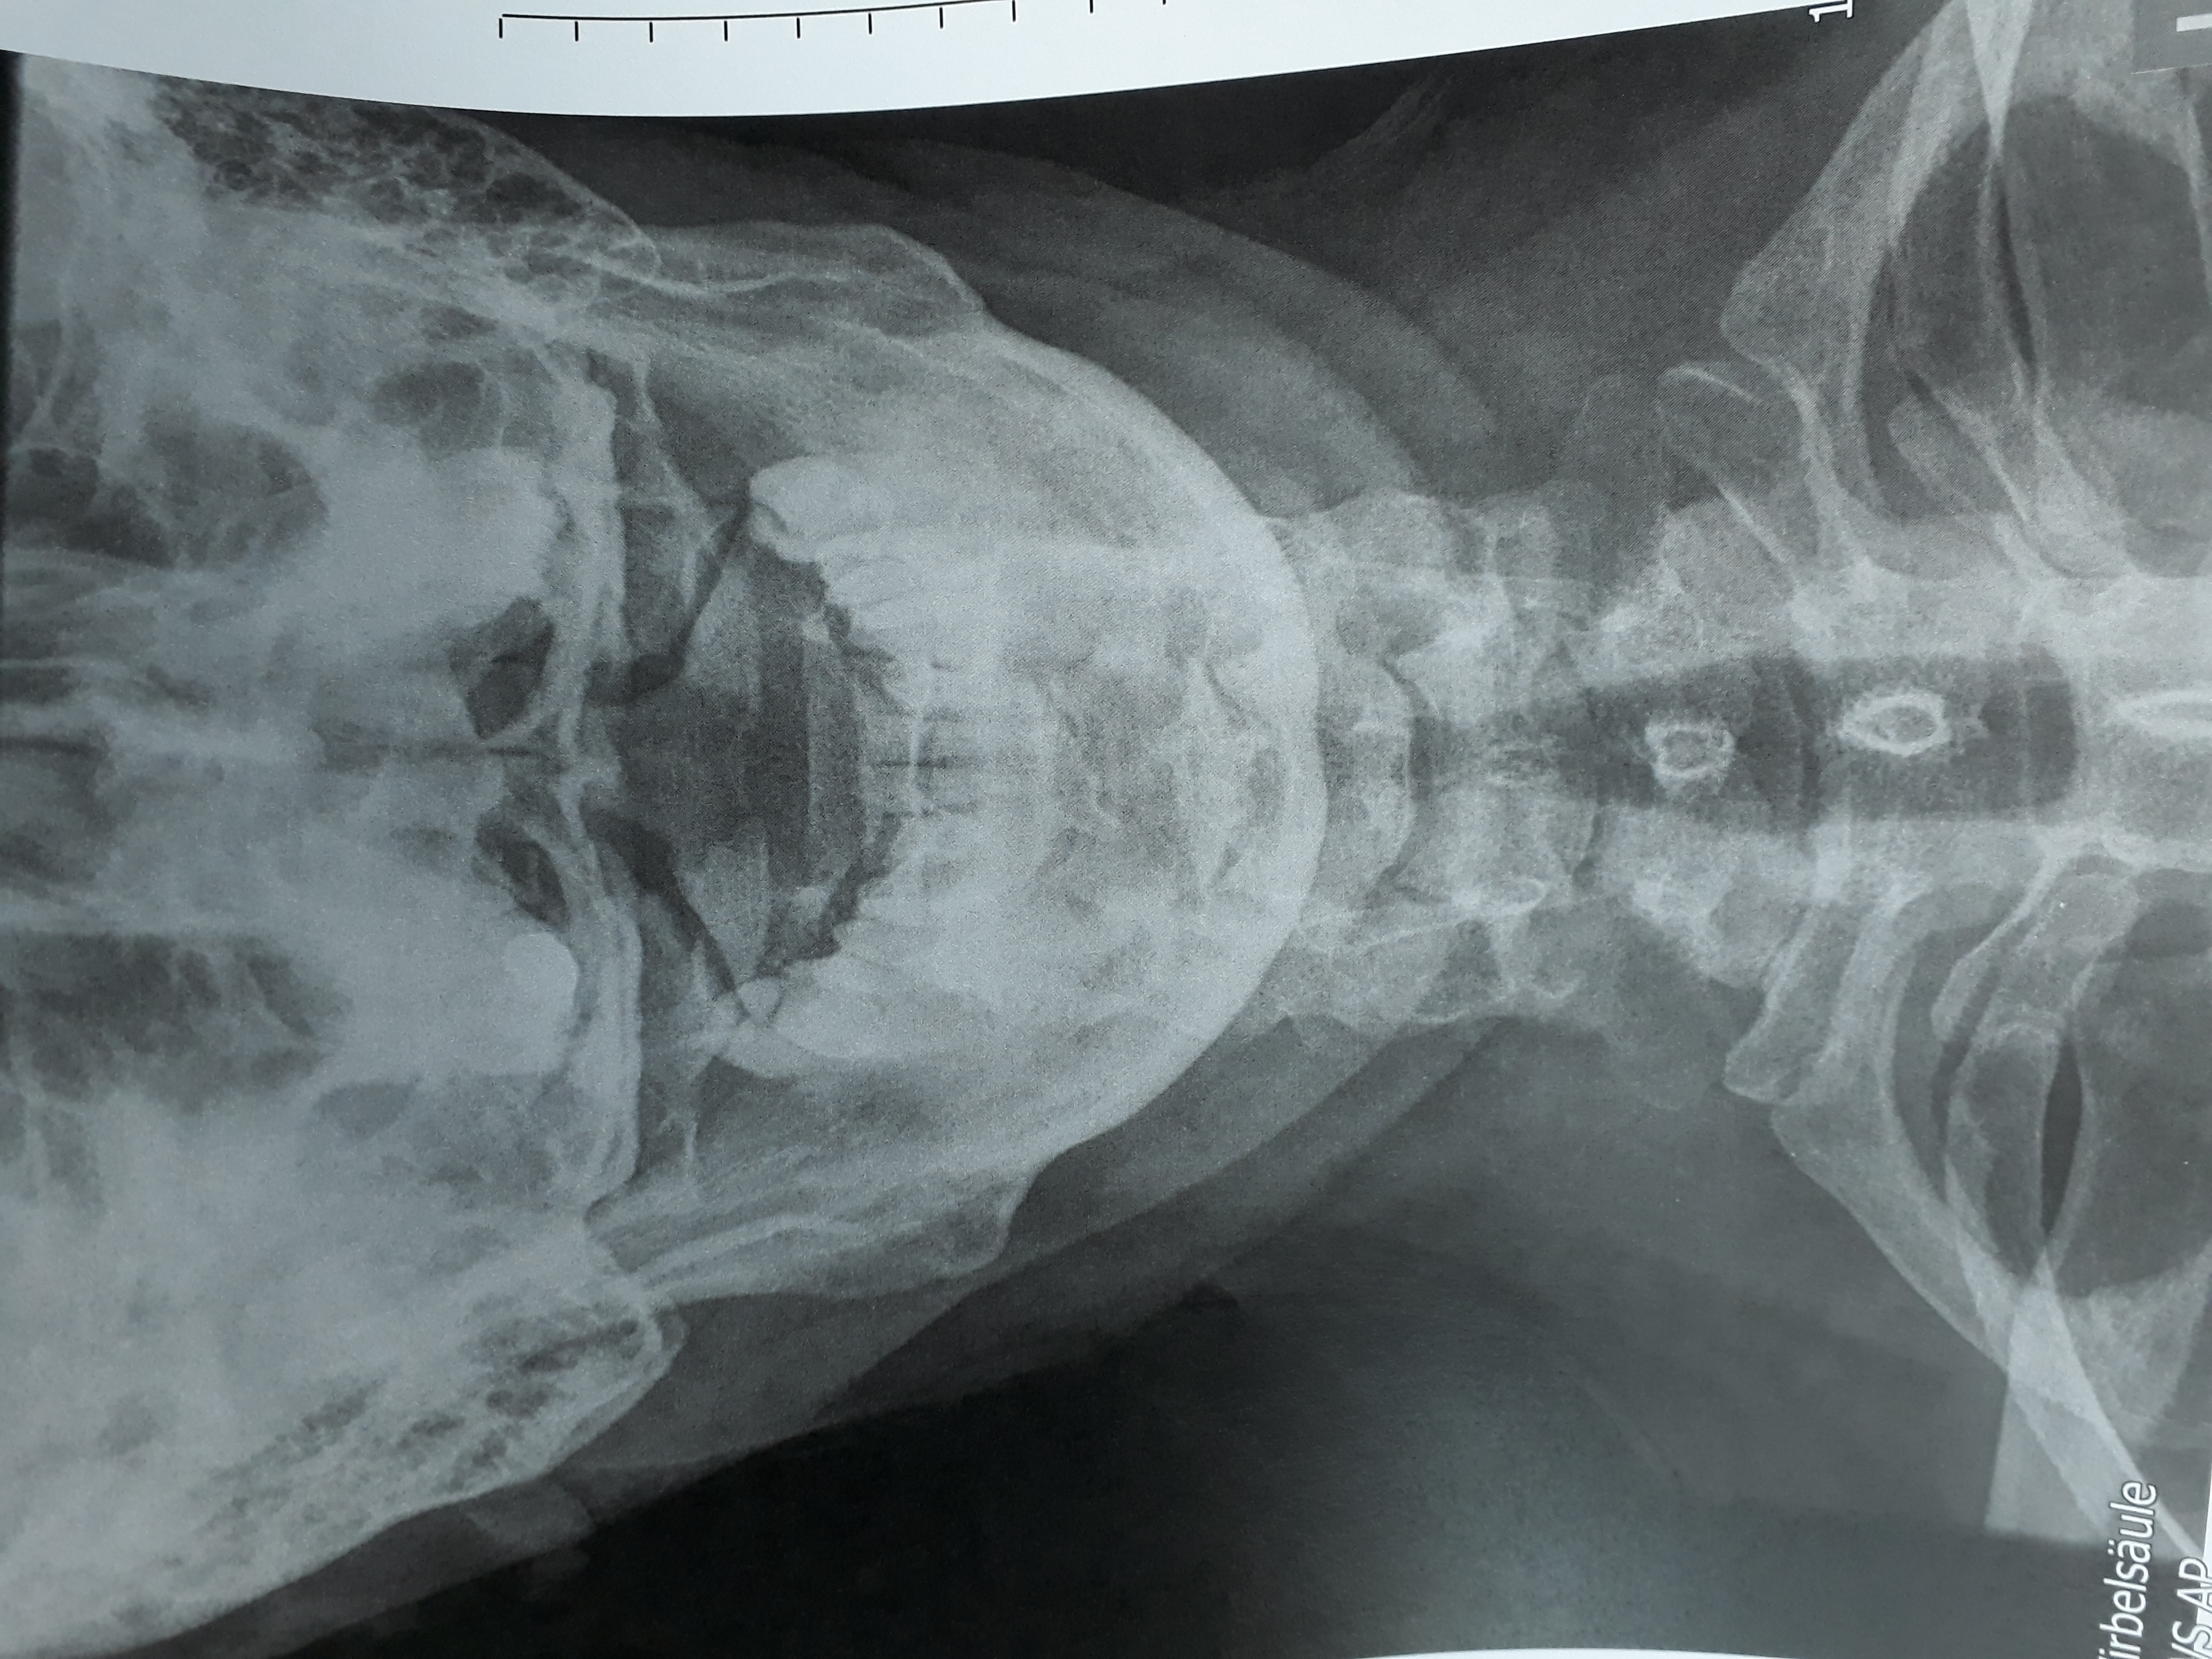

ich schicke mal ein Bild vom Röntgen. Ich bin der Meinung das der Abstand Dens-Atlas total unterschiedlich ist und es doppelt so grosse Abweichungen gibt.

Das lässt sich so etwas schwierig beurteilen da es nur zweidimensional ist, an einem Körper sind auch nur wenige Strukturen wirklich gerade beziehungsweise gleichmäßig, am einfachsten ist es die Stellung mal abtasten zu lassen…

Dens scheint ziemlich zentriert zu sein. Was auffällig ist, ist die HWS-Steilstellung.

kann diese Steilstellung der HWS auch mit dem Atlas zusammenhängen?

Mich irritiert der Abstand zwischen atlas-dens ( links) zu atlas-dens ( rechts)

Dens ist ok, ist nicht das Problem.